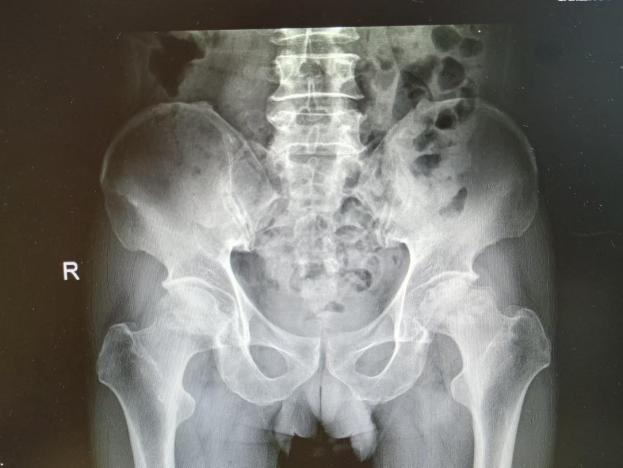

多年来,贵州航天医院各科室紧跟医学前沿,不断强技术、补短板,大力开展新技术、新项目,完成了许多高精尖、高难度、本地区“首例”的技术,填补了医院医疗技术空白,满足了群众日益增长的医疗需求。 贵州航天医院骨科率先在遵义地区开展骨搬移技术,截至目前,已治愈慢性骨髓炎、感染性骨不连、骨缺损、脉管炎、糖尿病足患者200余例,糖尿病足治疗保肢率达到98%。 本期,我们将为大家带来骨科特色技术——骨搬移技术(Ilizarov)。 案例分享 一名59岁的患者,身患糖尿病12年,在来我院3个月前出现了右脚溃烂的症状,来院就诊时,患者的右脚十分红肿,右脚脚趾坏死,伤口处不断流出黑红色脓液,情况十分严重。在接诊到患者时,骨科专家团队高度重视,立刻为患者完善了CT血管造影(CTA)等相关检查,诊断为:2型糖尿病,糖尿病周围血管病变,右糖尿病足。 术 前 考虑到患者情况比较严重,为最大限度保证患者肢体完整,科室专家团队进行了严格的讨论评估,为患者制定了骨搬移技术治疗方案,在征得患者及其家属的同意后,成功通过搬移骨块为患者进行治疗,促进患者病变肢体血管再生。 胫骨横向骨搬移外架固定 清除感染病灶 术后调节外架,通过搬移骨块 促进患肢血管再生 患者在术后三周前来换药,观察到感染得到进一步控制;术后六周复查,患者病变处已愈合,进行CT血管造影(CTA)后可明显观察到足部血管再生。 术后3周 术后6周愈合 CT血管造影见足部血管再生 糖尿病患者全身与局部的问题互为影响,形成恶性循环,糖尿病足溃疡创面迁延不愈,常见干性坏疽、湿性坏疽、趾坏死、深且大的溃疡以及骨髓炎等症状,还可导致脓毒血症,以往为保全生命,患者被迫选择一次或多次截肢。骨搬移技术的发展进步,能在血糖有效控制、局部有效清创下,有效促进患肢微血管再生,改善患肢血供,达到糖尿病足更快治疗康复的目的,并能根据病变情况最大限度的保障患者肢体完整。 什么是骨搬移技术 骨搬移技术是通过使用专用的骨外固定器固定骨段,每天缓慢牵拉,在牵拉搬移过程中,骨段尾部形成新骨及新的软组织,从而修复骨骼缺损及软组织缺损。是治疗大段骨缺损、骨不连、骨感染、肢体畸形的金标准方法,也用于治疗脉管炎、糖尿病足等肢体缺血性疾病。 骨感染缺损 切除感染段 搬移骨段 新骨形成 骨感染根治愈合 骨搬移技术原理 生物组织在持续、稳定、缓慢牵拉下,能刺激细胞分裂、组织再生,骨外固定技术运用该原理,通过持续缓慢调节外固定器形成牵拉张力,促进牵引成骨与相邻组织再生,如神经、血管、肌肉、皮肤等再生,达到治疗大段骨缺损、肢体缺血如糖尿病足等疾病的目的。 骨搬移技术优势 (一)除治疗骨缺损、骨不连外,有更广的适用范围,利用组织再生、血管再生等特性,能大量运用于肢体畸形的矫形、糖尿病足等的治疗。 (二)治疗效果确切,重建肢体外型和功能,极大降低截肢率和残疾率。 (三)明显提高了患者生活质量,极大减轻其家庭及社会负担。 肢体畸形的矫形 慢性骨髓炎 骨段切除 术后1年 濒临截肢的脉管炎术后6周 难愈创面术后3周 贵州航天医院骨科 专家团队 赵学平 骨科主任 主任医师 临床擅长:从事骨科临床工作30余年,对骨科常见疾病的诊治具有丰富的临床经验。 世界中医药联合会脊柱康复专业委员会常务理事,中华中医药学会整脊分会常务委员,中国中西医结合学会骨伤科分会肢体矫形功能重建与康复专家委员会常务委员,中国研究性医院学会骨科创新与转换专业委员会关节外科学组保髋工作委员会常委,中国康复技术转化及发展促进会骨外科与康复技术转化专业委员会常务委员,泛珠三角区域运动医学联盟(PPRD-SMA)理事会常务理事,中国研究型医院学会运动医学专业委员会委员,贵州省中医药学会整脊分会副主任委员,贵州省中西医结合学会银质针专业委员会副主任委员,贵州省康复医学会骨与关节专业委员会常务委员,贵州省人民医院骨科专科联盟常务理事,贵州省康复医学会骨内科专业委员会常务委员,中华医学会贵州省骨科学会委员,贵州省康复医学会脊柱脊髓专业委员会常务委员,贵州省运动医学分会委员,贵州省康复医学会骨与软组织肿瘤专业委员会委员,遵义市医学会创伤分会副主任委员,贵州省康复医学会骨内科专业委员会遵义地区分会常务委员,遵义市医疗事故鉴定、伤残鉴定、工伤鉴定、司法鉴定专家。 长期从事骨科临床研究及教学工作,在国家级、省部级杂志发表论文20余篇,SCI论文2篇,参与主编骨科专著2部,主持省部级科研项目2项,参与指导省部级、市级科研项目6项。 陈明勇 骨科副主任 副主任医师 临床擅长:从事创伤骨科工作约20年,对骨缺损、骨不连、骨肿瘤、肢体畸形等的肢体矫形重建及功能重建,慢性化脓性骨髓炎的根治治疗、糖尿病足的保肢治疗、快速康复理念(ERAS)下的老年骨折的诊治,四肢复杂骨折的诊治,四肢骨折等微创手术治疗具有丰富的临床经验。 2004年毕业于遵义医学院临床专业,曾在中国人民解放军总医院、广西医科大学第一附属医院、上海第六人民医院骨科进修。中国中西医结合学会骨伤科专业委员会横向骨搬移治疗糖尿病足及微血管网再生学组首届委员,遵义市医学会创伤分会常务委员。 瞿 辉 骨科 副主任医师 临床擅长:对骨科的常见病、关节外科、脊柱外科及运动医学疾病的诊治具有丰富的临床经验,熟练掌握骨科手术操作技术。 毕业于遵义医学院临床医学系,2005年前往广州中山大学第一附院骨显微医学部进修学习,2011年前往成都华西医院进修学习,并多次在省内外学习骨科相关知识,是中华医学会骨科分会会员。 赵兴东 骨科 主任医师 临床擅长:擅长骨科的常见病及各种创伤、四肢骨折创伤修复、骨感染、手足疾病的诊治和手足体表畸形的矫形整复,熟练掌握骨科四肢骨病及创伤的手术操作技术,尤其在四肢关节复杂性损伤、手足外伤、组织缺损创面、难治创面的皮瓣修复方面及平足、高弓足矫形方面及四肢慢性疼痛诊治、康复方面具有丰富的临床经验。 硕士研究生,毕业于遵义医学院临床外科系,2015年前往山东省立医院手足外科进修学习;遵义市医学分会创伤分会第一、二届委员,遵义市手外科医学会第二委届员会常务委员;在省级及省级以上期刊发表文章9篇,参编著作2部,参与主持并完成市级课题1项,参与市级课题2项、省级课题1项。 张俊凯 骨科 副主任医师 临床擅长:从事骨科临床工作28年,对创伤骨折、骨感染、骨缺损、骨不连等外科诊治,四肢骨折的微创手术治疗,四肢复杂骨折(如关节内粉碎性骨折、多发骨折等)的损伤控制及手术治疗等具有丰富的临床经验。 1995年毕业于遵义医学院临床专业,2009年前往复旦大学附属医院骨科进修1年。 卢懿明 骨科 副主任医师 临床擅长:从事骨科工作18年,对创伤骨折、四肢骨折的微创手术治疗、四肢复杂骨折(如关节内粉碎性骨折、多发骨折等)的损伤控制及手术治疗,尤其是髋部骨折的PFNA等微创技术,踝关节骨折、膝关节周围骨折的Mipo微创技术等具有丰富的临床经验,开展了4项新技术,发明6项新型专利技术。 2005年毕业于遵义医学院临床专业,2017年,前往南方医科大学第三附属医院骨科进修半年,回院后运用Mipo技术对骨干骨折及干骺端骨折的治疗技术,同时积极开展骨盆骨折、髋臼骨折腹直肌外侧切口的应用;发表了多篇专业论文,经常参与省内外学术交流会授课,获得医院荣誉称号多个。 邬夏荣 骨科 副主任医师 临床擅长:从事骨科工作16年,对四肢复杂骨折、骨肿瘤的诊治,尤其是足踝创伤、慢性踝关节损伤、平足症等诊疗具有丰富的临床经验。 2006年毕业于遵义医科大学临床医学专业,曾在陆军军医大学西南医院进修学习,发表多篇骨科学术论文。 余德怀 骨科 副主任医师 临床擅长:从事骨科工作10余年,对运动医学、骨关节、脊柱外科常见病、多发病的诊治具有丰富的临床经验。 硕士研究生,2011年毕业于遵义医学院临床医学专业,曾前往遵义医科大学附属医院运动医学专业进修学习;是贵州省医学会运动医学分会青年委员,西部关节镜联盟委员;发表多篇骨科学术论文。 冯 乾 骨科 副主任医师 临床擅长:从事骨科工作近20年,熟练掌握骨科多发病及常见病的诊治,尤其对脊柱退变性疾病的诊断及治疗具有丰富的临床经验,主要研究脊柱微创相关治疗方式,能熟练开展椎间孔镜及VBE。 曾前往北京大学第三医院进修学习疼痛及椎间孔镜、首都医科大学友谊医院专业进修脊柱内镜;是贵州省康复医学会第三届脊柱脊髓专业委员会委员;发明专利3项、发表脊柱外科专业论文多篇。 张艳金 骨科 副主任医师 临床擅长:从事骨外科工作16年,对复合伤、多发伤的救治、四肢骨干骨折、关节周围骨折、骨肿瘤、骨髓炎等诊治具有丰富的临床经验。 中共党员,硕士研究生,2006年本科毕业于山西医科大学第二临床医学院,2011年研究生毕业于北京军区总医院;在“老年COPD患者合并髋部骨折的诊治”国际合作课题组研究两年,在老年髋部骨折的诊治方面具有丰富的经验,并发表论文6篇;承担遵义市级课题1项;承担遵义医科大学的临床教学工作,获得遵义医科大学优秀带教老师荣誉。编撰有《骨科疾病诊疗精粹》一书,开展2项新技术,编撰地方规范《务川自治县创伤骨科常见疾病诊疗规范》一书。 赵小锋 骨科 副主任医师 临床擅长:从事骨科临床工作11年,对骨科常见病、多发病诊疗有较为丰富的临床经验,擅长脊柱相关疾病诊断及治疗,尤其是颈、腰、腿疼痛疾病诊断及治疗,擅长胸腰椎骨折微创经皮穿刺内固定术、经皮穿刺椎体成形术、经皮穿刺脊柱内镜下腰椎间盘摘除术、单纯开创腰椎间盘摘除术、腰椎滑脱复位椎间植骨椎融合内固定术、腰椎管狭窄减压融合内固定术及人工髋、膝关节置换术等。 2012年毕业于遵义医学院外科学专业硕士研究生,2019年参加“遵义市115医学人才精英计划”于上海交通大学第一附属医院培训学习,2023年于北京大学第三人民医院脊柱外科进修学习,曾获得遵义市优秀医师荣誉称号。 遵义市手外科第一届委员,遵义市医学会创伤分会第一届委员,遵义市医学会创伤分会第二届委员,贵州省康复医学会第三届脊柱脊髓专业会委员,遵义市医学会烧伤与整形外科学分会委员,发表论文5篇,其中国家级核心期刊1篇,SCI论文1篇,主持市级课题1项并结题,参与市级课题2项。 贵州航天医院骨科简介 基本情况 贵州航天医院(原3417医院)骨科组建于1968年,前身是以创伤和断肢(断指)再植闻名于世的上海市第六人民医院骨科,中国断肢(断指)再植的奠基者、中科院院士陈仲伟等著名专家、学者多次莅临科室指导医疗、教,是贵州省最早拥有专业骨科技术科室之一,在70年代开展了贵州省首例断肢(断指)再植手术。组建50余年来,诊治患者已逾百万,挽救了无数的伤病员,成为了保障遵义地区人民群众健康的重要支撑。 经过几代人的不懈努力,今天的骨科,已由创伤骨科发展至骨病、骨肿瘤、骨结核等领域,现有脊柱外科、关节外科、四肢创伤、手足外科四个亚专科,成为了集医疗、教学、科研于一体的综合学科,是贵州省临床重点专科、遵义市临床重点专科、遵义市骨科临床医学中心、遵义市基层骨科专科联盟理事长单位。 科室目前开放床位110张,共有医护人员50余人,副高级以上专家18人,硕士研究生15人。拥有一流骨科医疗设备多台,每年不定期选派优秀技术骨干到全国各大知名医学院校进修、学习、参观、交流,并邀请国内、国外知名专家教授来院进行交流、指导,通过不断引进国内外先进的诊疗技术,科室医疗技术水平稳步提升,为广大人民群众提供了优质的医疗服务。 专科特色 骨一科 (一)骨缺损、骨不连的肢体与功能重建 胫骨横向骨搬移技术治疗糖尿病足: (二)慢性骨髓炎的根治治疗 (三)肢体缺血性疾病如糖尿病足、脉管炎的保肢治疗 (四)皮瓣修复 (五)复杂创伤的治疗 (六)老年髋部骨折及小儿骨折快速手术 老年髋部骨折: 骨二科 (一)胸腰椎骨折微创经皮椎弓根螺钉固定术 (二)老年性骨质疏松性患者腰椎滑脱脊柱内固定术(骨水泥螺钉) (三)V形双通道脊柱内镜技术(VBE)腰椎融合术治疗腰椎退行性疾病 (四)老年性骨质疏松性骨折(PVP/PKP)术 (五)人工髋关节置换术 (六)双侧股骨头坏死人工全髋关节置换 (七)右侧全髋置换术后假体周围骨折翻修 (八)人工膝关节置换术 (九)人工膝关节假体松动翻修 (十)关节镜技术 传统手术切口 关节镜技术切口 诊疗范围 骨一科 1.四肢创伤、矫形。 2.手、足踝外科。 骨二科